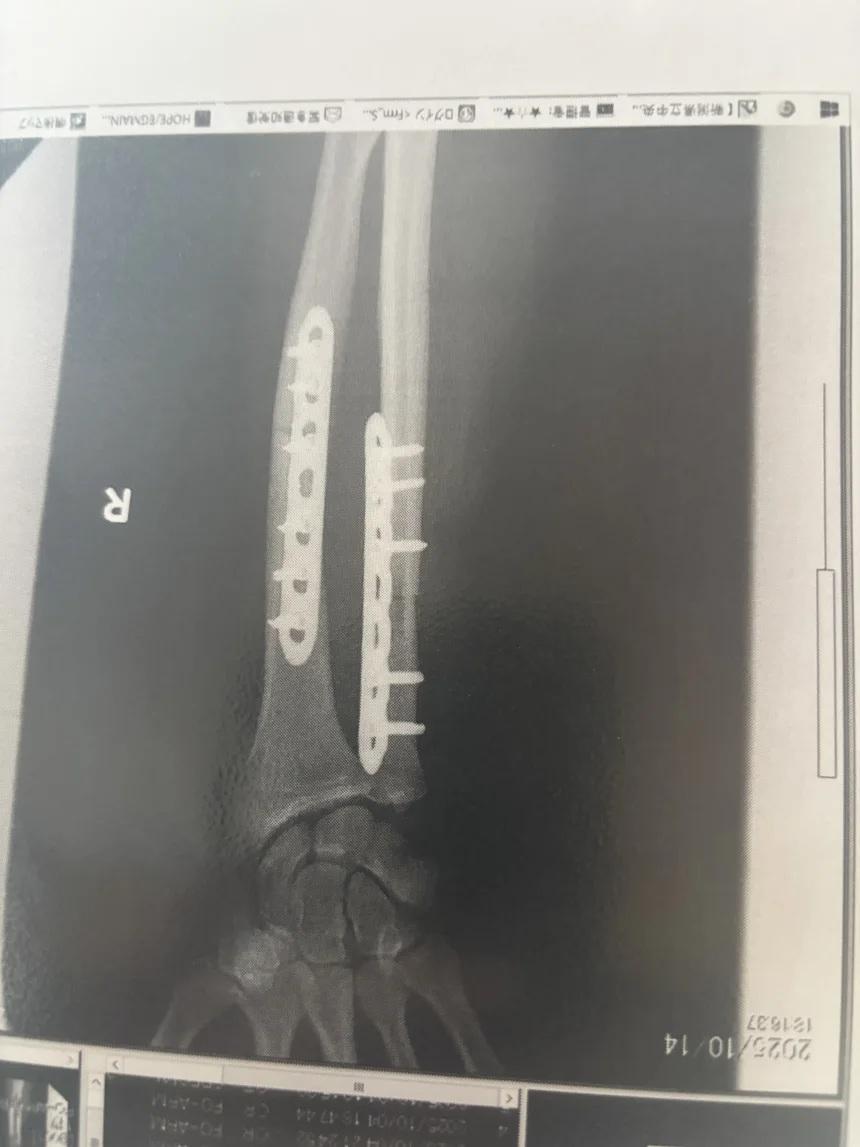

Halloran在病床上向CNN記者稱,接受了3次手術,包括骨移植以填補遭咬斷的骨,以及在手臂裝入金屬板,距離身體完全康復還有一段漫長時間,他原要進行馬拉松訓練。除了身體,受襲留下的心理陰影也巨大,他說如滑浪手遭鯊魚襲擊後害怕回到海裡。不過,他決定康復後會回到叢林跑步,這要感謝當地跑手社區團體的支持,而他能夠撿回一命,已較其他人幸運。